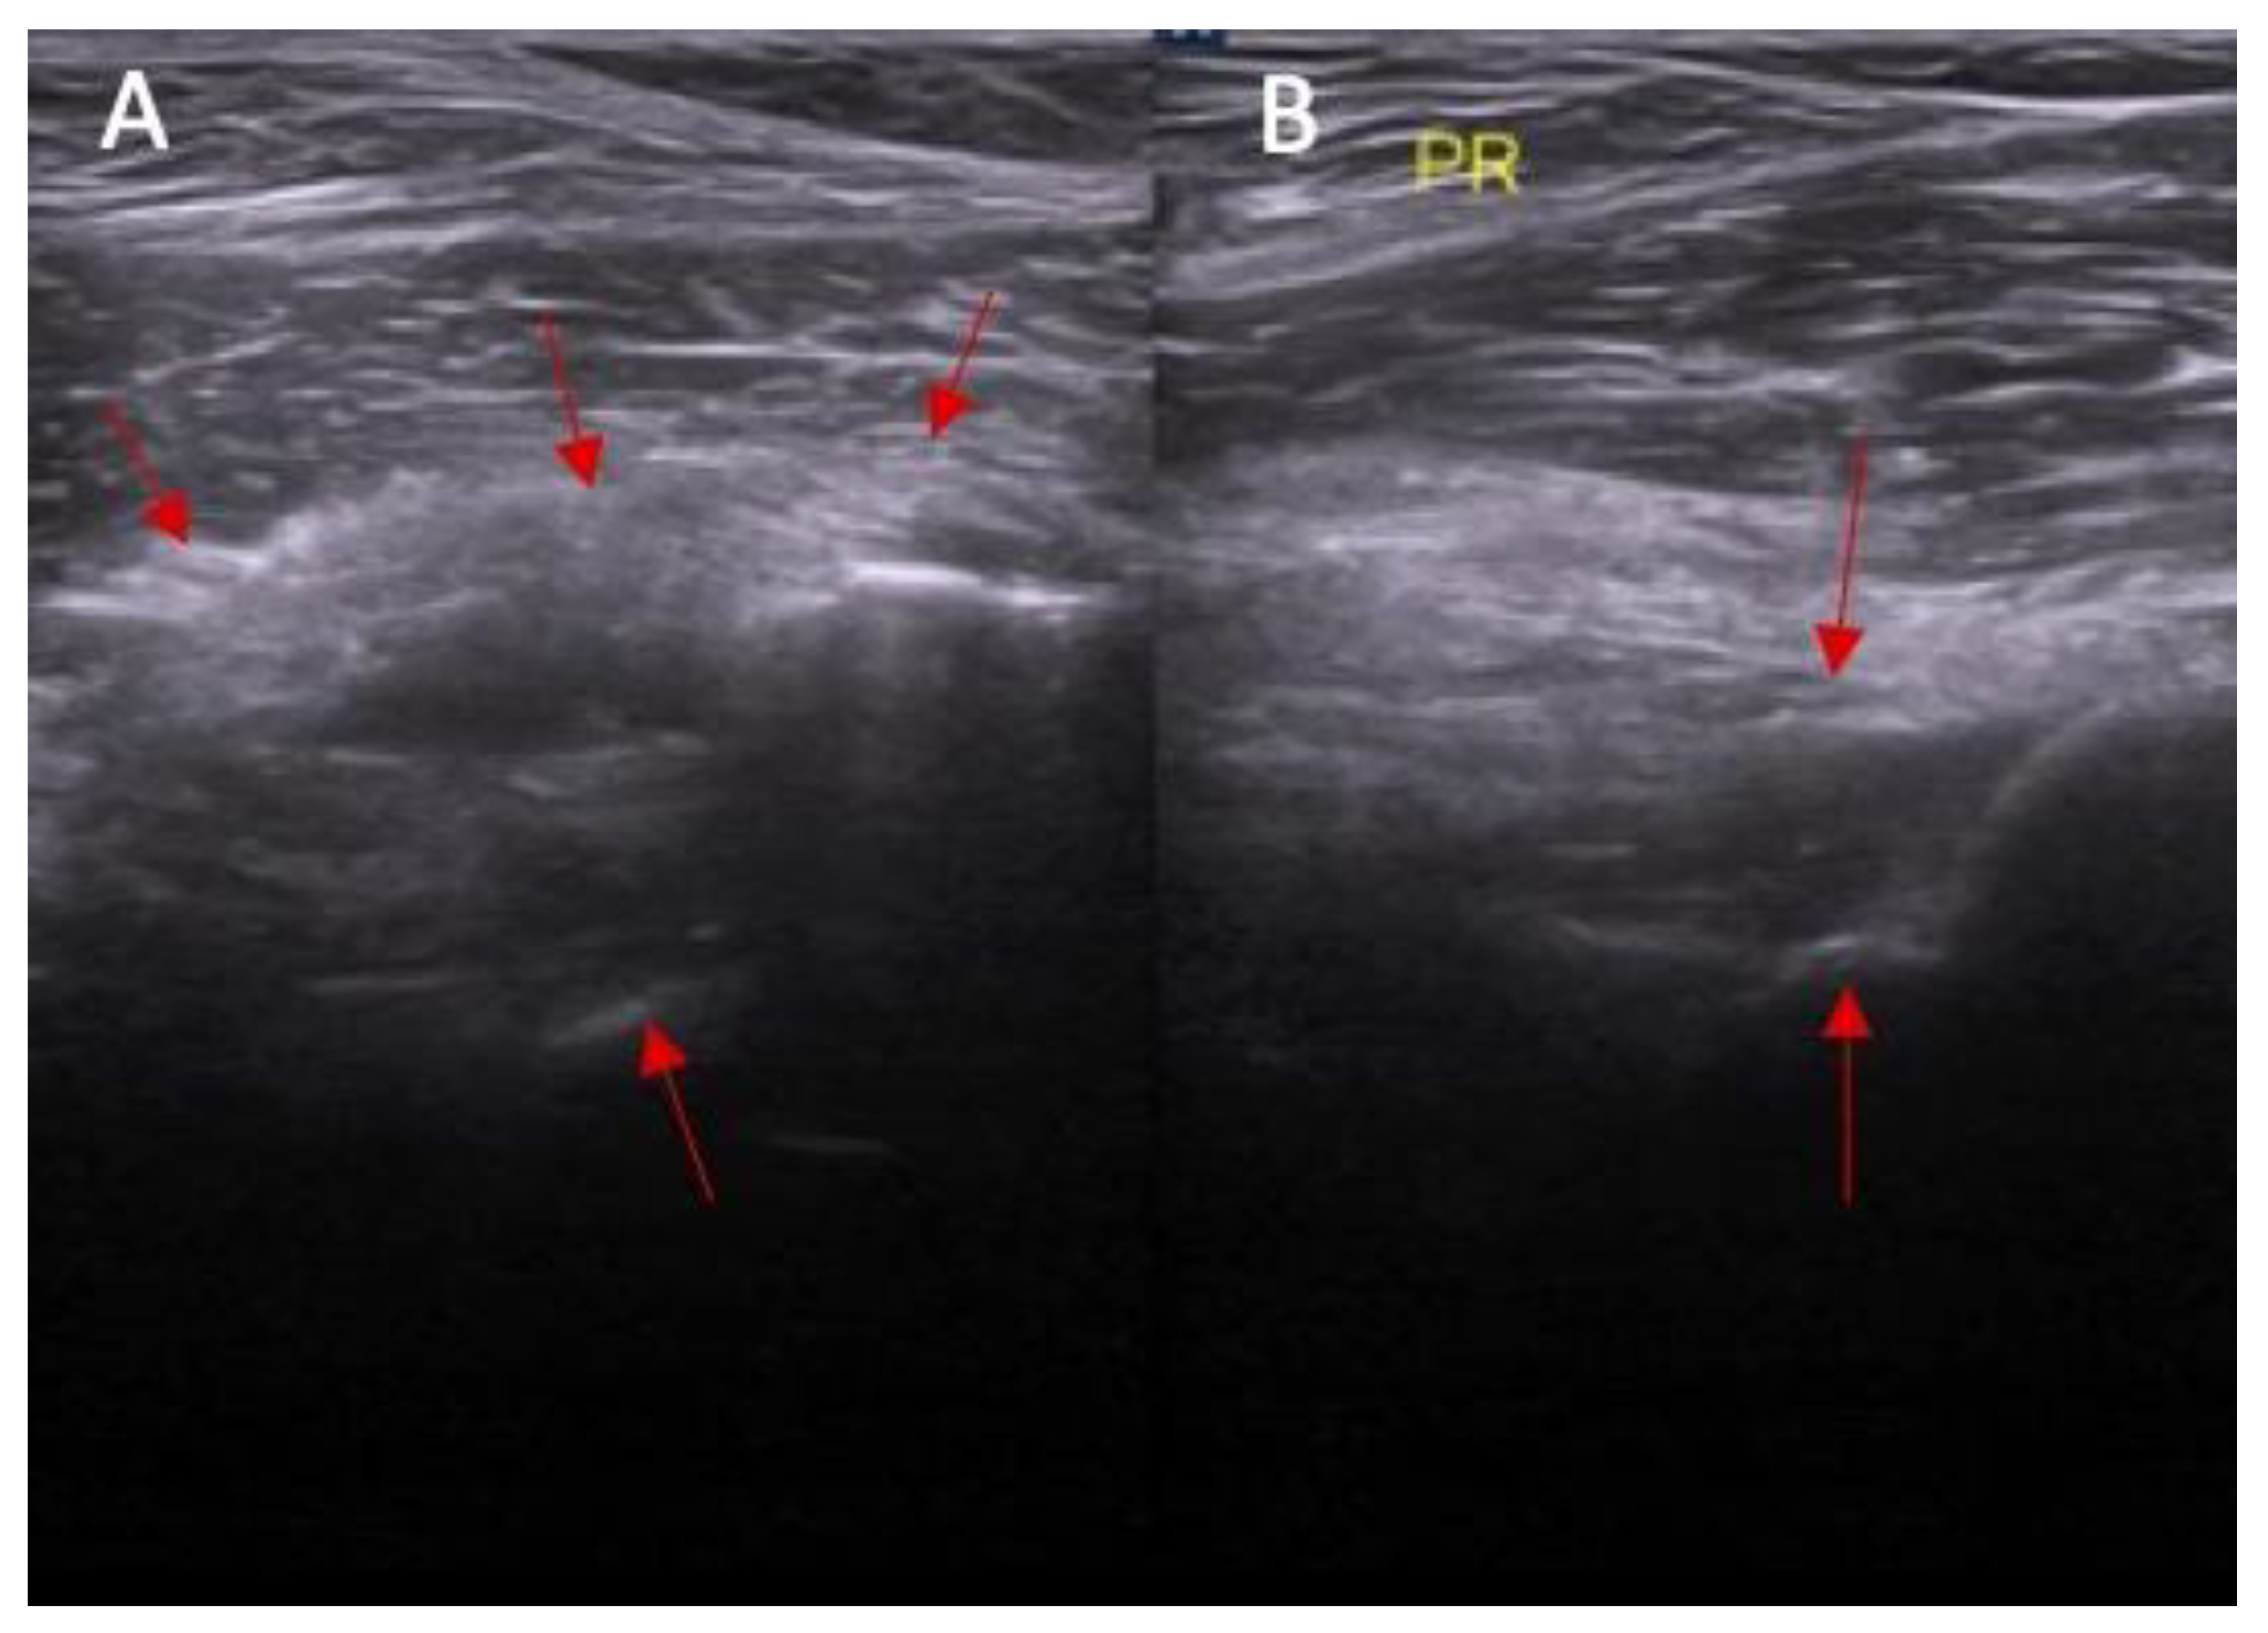

Figure 6.

(A) Ultrasound view of swelling/scarifications of the ACL/PCL compartment with change of the morphology of the posterior joint capsule complex marked with the arrows and (B) normal view. PR—right.

Swelling of the ACL/PCL on ultrasound was more common in patients with an ACL injury than in those without an ACL injury (88% vs. 0%, respectively, and p < 0.0001) (Figure 6 and Figure 7). OR = incalculable.